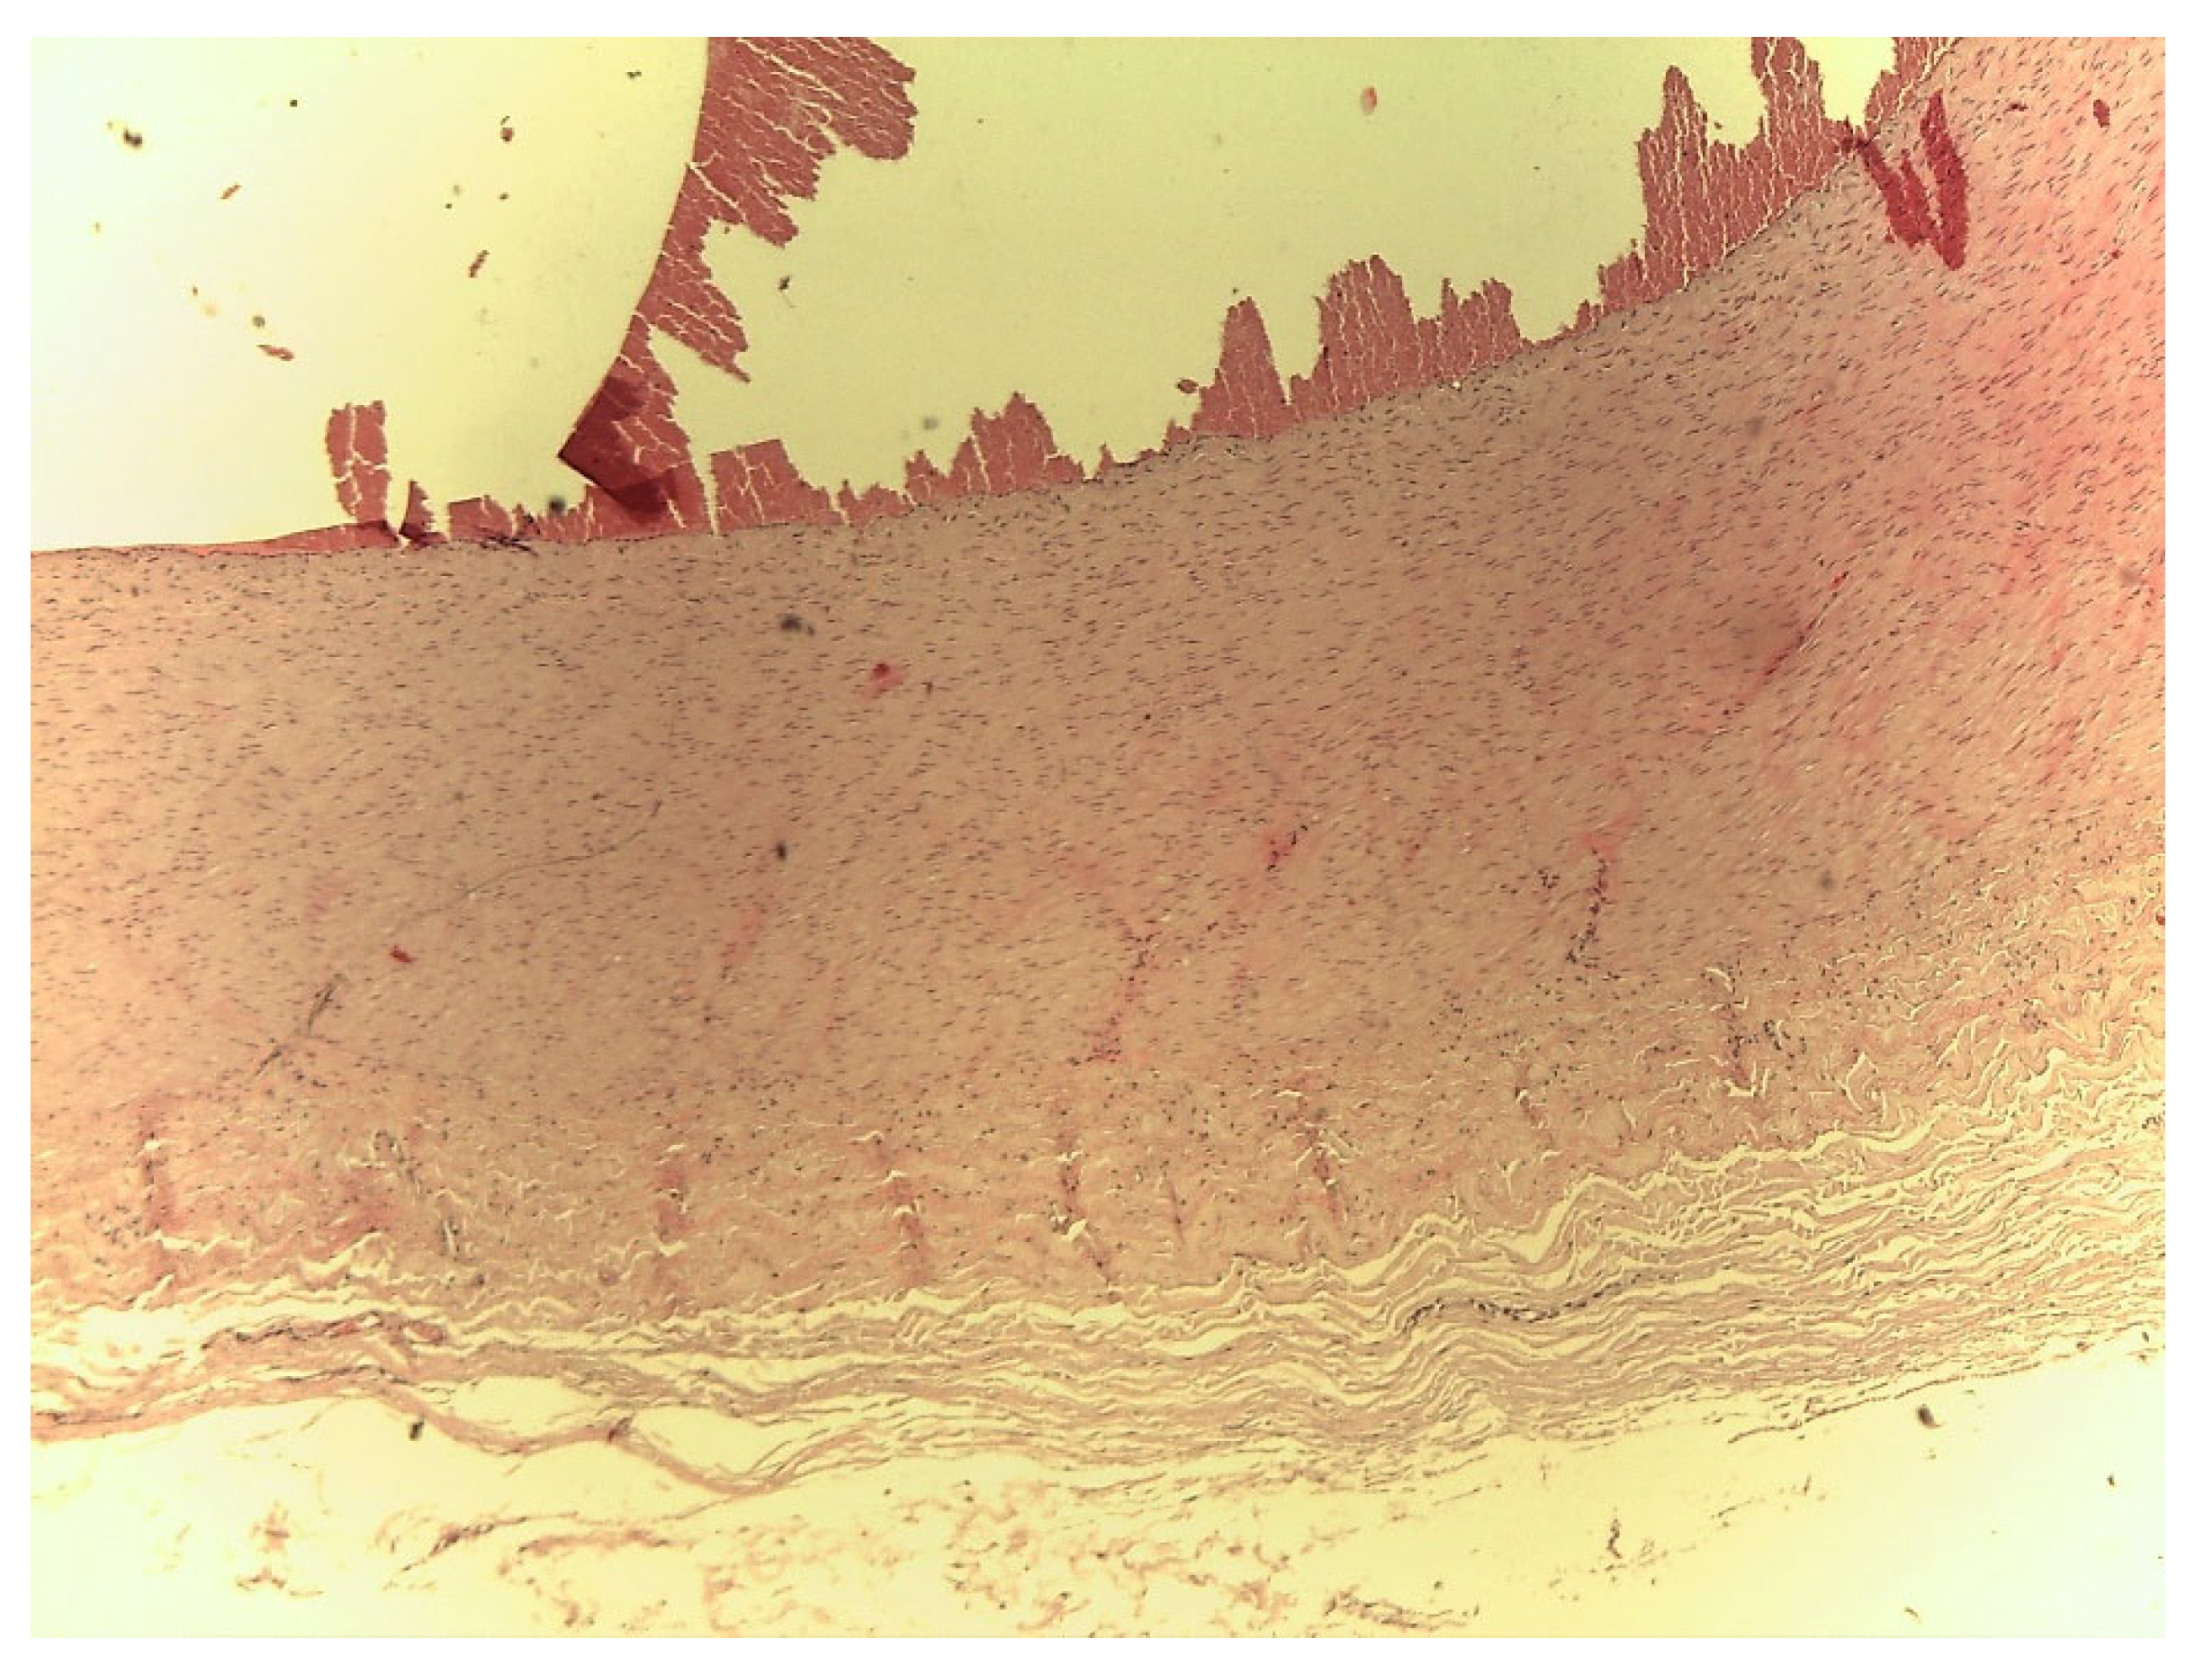

Histopathology

The histological test showed no differences between the three different neck cutting locations. In general, fragments of a clot could be seen lying on the vascular endothelium, arranged in an irregular fashion (Figure 2) and evident distension of the elastic and muscular fibres, characterized in some areas by irregularity and interruption (Figure 3). Moreover, swelling at the distal end of the artery was associated with erythrocytes and fibrin trapped within the connective tissue sheath surrounding the artery. On the other hand, there were no signs of blood infiltration within the artery wall, suggesting that this formation was not a true aneurysm.

Figure 2.

Bovine carotid artery with false aneurysm. Haematoxylin–Eosin (H.E.) (20×).